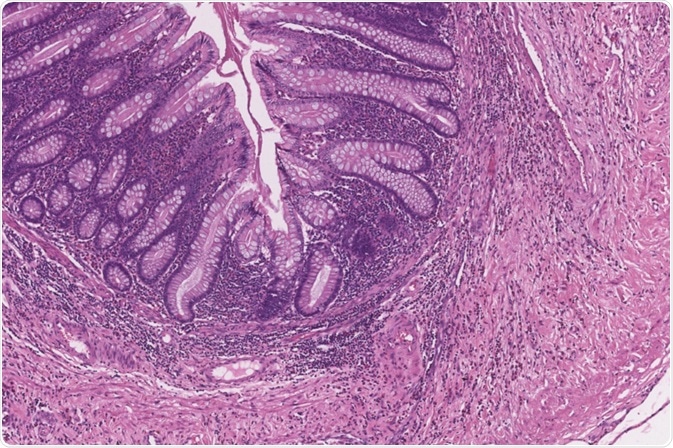

Image Credit: Java Jar/Shutterstock.com